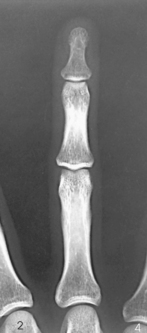

Structures shown: A PA projection of the appropriate digit is visualized (Figs. 4-16 through 4-19).

Structures shown: A lateral projection of the affected digit is shown (Figs. 4-24 through 4-27).